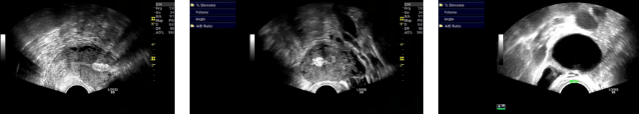

2023-11-22 子宫三维超声:子宫右角部见15mm*9mm高回声团,CDFI:可见星点状血流信号。内膜厚度3mm,清晰居中。子宫右侧旁见65mm*36mm无回声,内见多条分隔,CDFI:未见明显血流信号。周边似见少许卵巢组织回声。子宫三维成像:宫腔偏右侧角部可见一高回声团,右侧几近达浆膜层。提示:子宫右角部高回声团、右附件区囊性包块。

入院后完善复辅助检查,于2023-11-26日拟行宫腔镜检查+TCRF。宫腔镜检查中发现宫腔右半宫腔封闭,检查镜钝性分离封闭宫腔过程中发现宫底近右侧角部陈旧性穿孔,有肠管嵌顿入宫腔内与子宫后壁致密粘连。